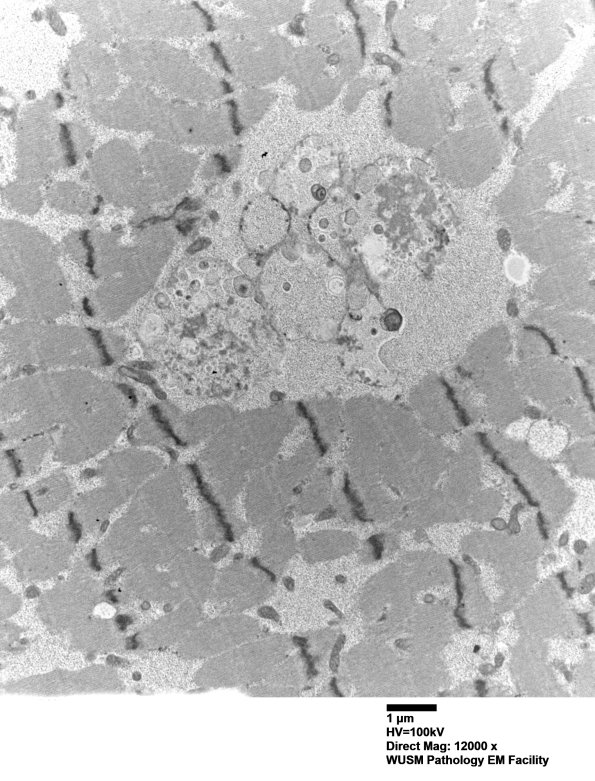

Washington University Experience | METABOLIC | Pompe Disease | 5D11 Muscle (Case 5) EM022 - Copy

5D11,12 The cytosomes here are a mixture of the previous elements with both free and membrane bound glycogen. (electron micrographs)